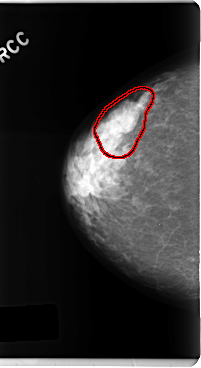

FILE: C_0247_1.RIGHT_CC.OVERLAY

TOTAL_ABNORMALITIES 1

ABNORMALITY 1

LESION_TYPE MASS SHAPE LOBULATED MARGINS ILL_DEFINED

ASSESSMENT 3

SUBTLETY 3

PATHOLOGY BENIGN

TOTAL_OUTLINES 1

BOUNDARY